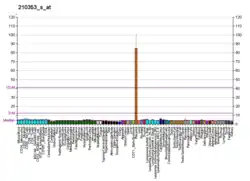

The norepinephrine transporter gene, SLC6A2 is located on human chromosome 16 locus 16q12.2. This gene is encoded by 14 exons.[7] Based on the nucleotide and amino acid sequence, the NET transporter consists of 617 amino acids with 12 membrane-spanning domains. The structural organization of NET is highly homologous to other members of a sodium/chloride-dependent family of neurotransmitter transporters, including dopamine, epinephrine, serotonin and GABA transporters.[7]